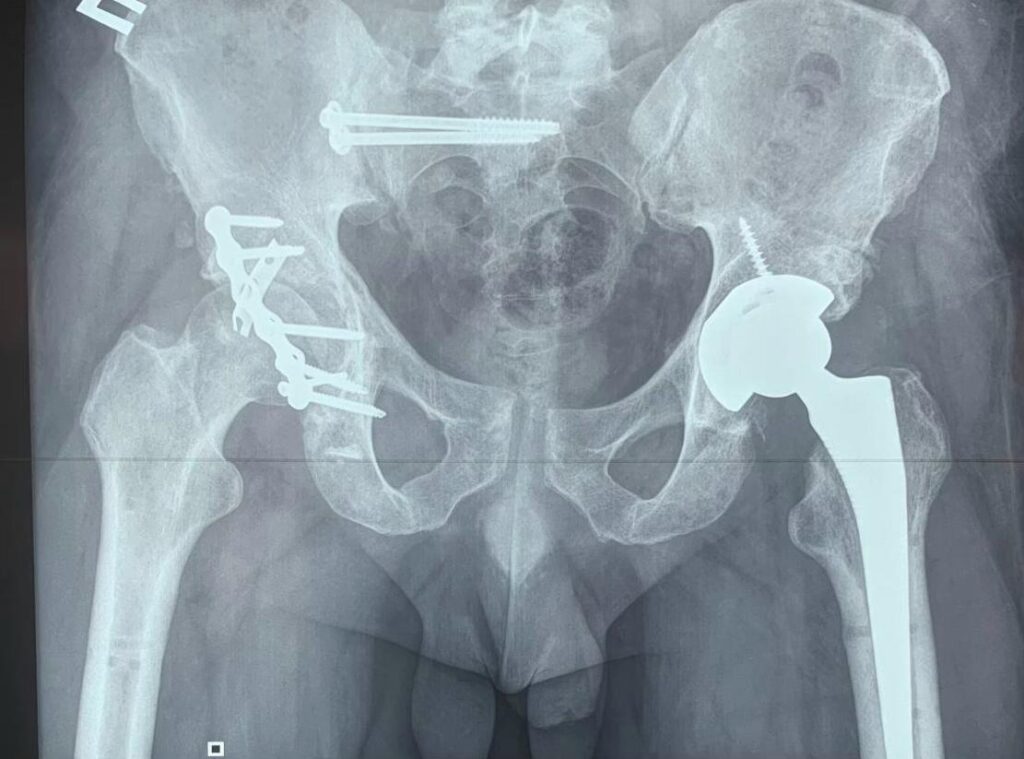

Наша лікарня є одним із небагатьох медичних центрів в Україні, де надають допомогу пацієнтам із важкими травмами та переломами кісток тазу ![]()

Такі травми потребують високої кваліфікації, сучасного обладнання та злагодженої роботи команди лікарів. У нашій лікарні застосовуються сучасні хірургічні методи, які дозволяють стабілізувати стан пацієнта, відновити функції та повернути його до активного життя ![]()

Ми беремося за випадки, які потребують особливої уваги та досвіду, і робимо все можливе для повноцінного відновлення пацієнтів ![]()